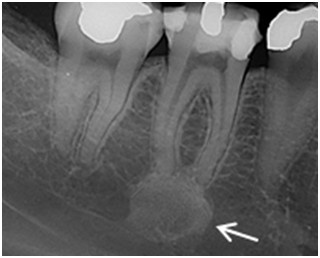

Jaką zmianę przedstawia radiogram?

Pytanie 44